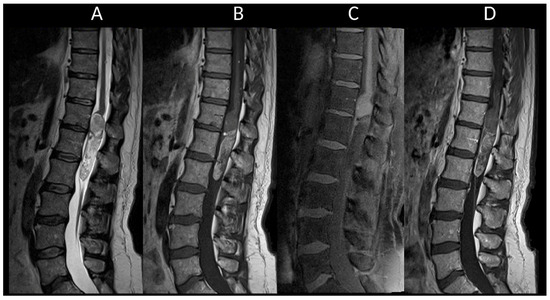

3.2. Degenerative Compressive Myelopathy

3.3. Vascular Myelopathies